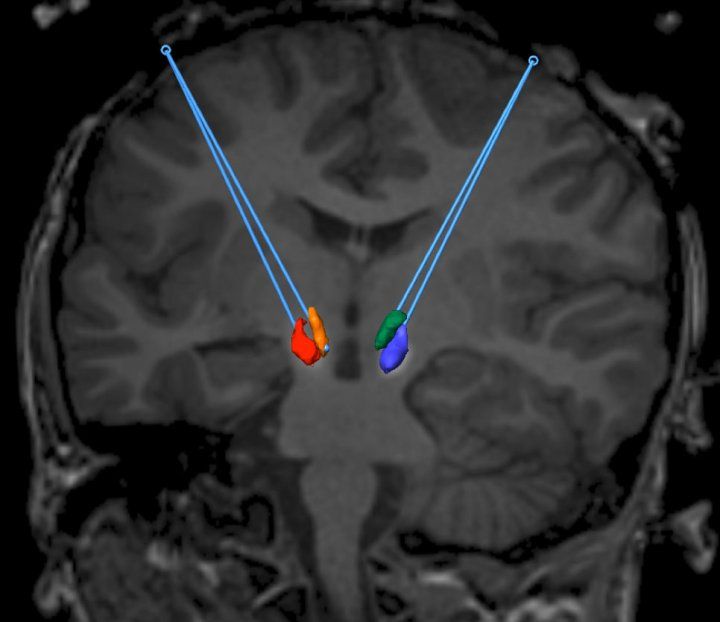

In AADC deficiency the children lack a critical enzyme that helps the brain make serotonin and dopamine, so called “chemical messengers” that help the cells in the brain communicate with each other. In his AADC clinical trial Dr. Bankiewicz and his team created a tiny opening in the skull and then inserted a functional copy of the AADC gene into two regions of the brain thought to have most benefit – the substantia nigra and ventral tegmental area of the brainstem.